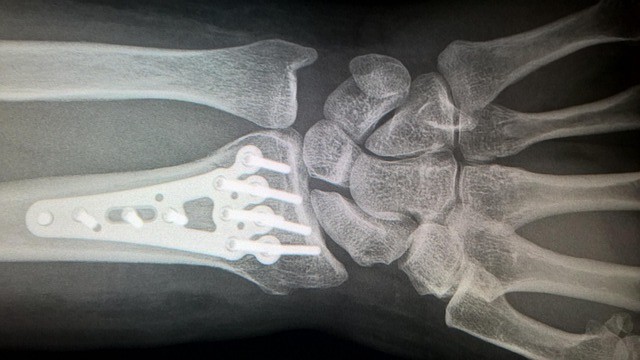

A wrist fracture refers to a break in one or more of the bones around the wrist joint, most commonly the distal end of the radius. Because the wrist plays a key role in hand movement, grip strength an...